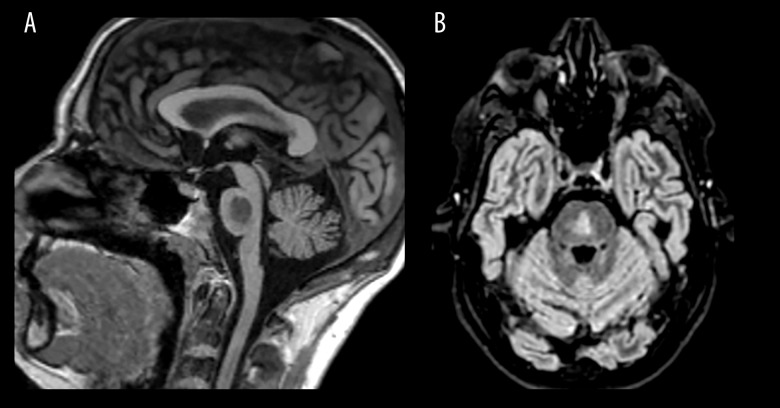

BACKGROUND Central pontine myelinolysis (CPM) is an osmotic demyelination syndrome most commonly observed in patients with chronic hyponatremia who undergo rapid serum sodium correction. Risk factors for CPM include malnutrition, hypokalemia, advanced liver disease, hyperemesis gravidarum, and alcohol use disorder. In this case report, we present an unusual case of CPM in a 30-year-old man with alcohol use disorder who did not have hyponatremia during hospitalization and had no history of chronic hyponatremia. CASE REPORT A 30-year-old man was admitted to the hospital for alcohol detoxification. He presented with symptoms of alcohol withdrawal and distal lower-limb pain, accompanied by bilateral edema. After his withdrawal symptoms were controlled, persistent neurological abnormalities prompted an MRI, which revealed lesions suggestive of central pontine myelinolysis (CPM). The patient did not exhibit hyponatremia during his hospital stay. However, he had multiple previously identified risk factors for CPM, including significant alcohol consumption leading to malnutrition and refeeding syndrome-associated hypokalemia. The neurological exam performed 1 month after the onset of symptoms showed a favorable outcome without signs of dystonia or cerebellar syndrome, but with persistent left-wrist extrapyramidal rigidity. CONCLUSIONS This case report highlights the importance of a thorough neurological examination in patients with alcohol use disorder, to prevent falsely attributing neurological symptoms to alcohol intoxication. Clinicians should remain vigilant about the risk of CPM in patients with alcohol use disorder, even in the absence of hyponatremia, considering that other metabolic disturbances can contribute to its pathogenesis.